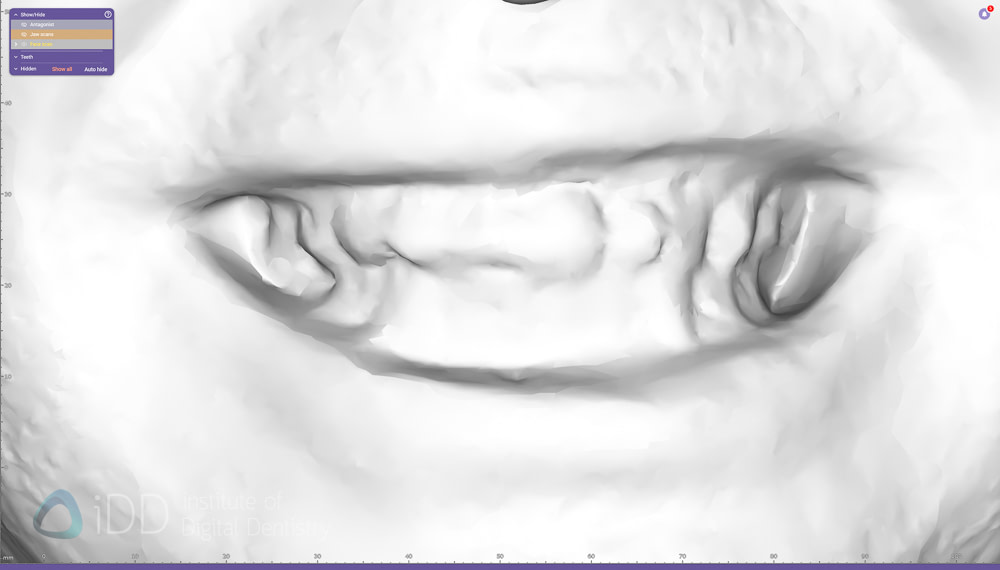

As mentioned above, the colour doesn't mean a lot at all. These scans only serve a purpose if we can align IOS with them, so we must disable colors and examine the definition on the teeth - as aligning IOS and face scans is similar to aligning any other data sets in digital dentistry - by identifying common points in both.

Also note the distortion in the face scanning with iPhone apps. It is interesting to see how the edges of the teeth are not exactly perfect. How much does this impact the alignment of IOS? Let's check without colour.

RayFace

Original Qlone

MetiSmile

Qlone Dental Pro

A few things stick out straight away. Obviously the dental specific scanners like RayFace and Metismile do the best. Very good details especially by RayFace but MetiSmile also did well and is one quarter of the cost.

The iPhone apps don't do as well and don't seem to have the resolution. With the original Qlone app you can see the downfall of this and many iPhone apps that are used to take a face scan. Although they can make the colour image look good, when you turn off the colour, you can clearly see the issues. How do you align an intraoral scan to this confidently?

In saying that, the new Qlone Dental Pro is a big improvement no doubt. So these are not just marketing claims. The new app really does capture the teeth and lips to a higher detail - but this cannot be thanks to hardware as I am using the same phone - it must be just smarter algorithms.

Although with the new app there is much more detail to be seen, the question is - does this look like the patient's actual teeth?

Aligning the IOS data to the face scan data is simple - by choosing multiple points of reference on both data sets. You are trying to find the same points on both the IOS and face scan, so the clearer the face scan, the easier and more accurate this is.

Therefore, the better the details of the teeth on the face scan, the more likely it is going to be an accurate alignment. And if you're going to rely on this for your cosmetic wax up etc, you want this as accurate as possible.